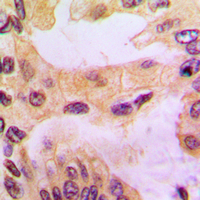

Immunohistochemical analysis of Cathepsin D staining in human liver cancer formalin fixed paraffin embedded tissue section. The section was pre-treated using heat mediated antigen retrieval with sodium citrate buffer (pH 6.0). The section was then incubated with the antibody at room temperature and detected using an HRP conjugated compact polymer system. DAB was used as the chromogen. The section was then counterstained with haematoxylin and mounted with DPX. -